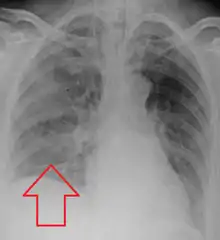

Location

Aspiration pneumonia is typically diagnosed by a combination of clinical circumstances (people with risk factors for aspiration) and radiologic findings (an infiltrate in the proper location).[1] A chest x-ray is typically performed in cases where any pneumonia is suspected, including aspiration pneumonia.[16] Findings on chest x-ray supportive of aspiration pneumonia include localized consolidation depending on the patient's position when the aspiration occurred.[17] For example, people that are supine when they aspirate often develop consolidation in the right lower lobe of the lung.[17] Sputum cultures are not used for diagnosing aspiration pneumonia because of the high risk of contamination.[18] Clinical symptoms may also increase suspicion of aspiration pneumonia, including new difficulty breathing and fever after an aspiration event.[5] Likewise, physical exam findings such as altered breath sounds heard in the affected lung fields may also be suggestive of aspiration pneumonia.[5] Some cases of aspiration pneumonia are caused by aspiration of food particles or other particulate substances like pill fragments; these can be diagnosed by pathologists on lung biopsy specimens.[19]